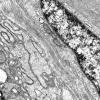

2D4 W20-8226A  (Case 2) EM 032 - Copy